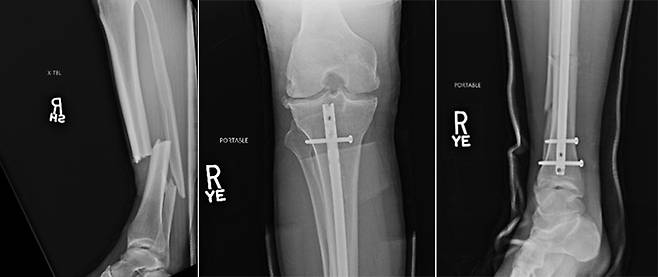

실바가 강하게 찬 로킥이 크리스 와이드먼(36, 미국)이 방어하려고 세운 무릎에 딱 걸렸다. 순간 왼쪽 정강이가 완전히 부러져 버렸다.

사람의 정강이에는 정강뼈와 종아리뼈가 있다. 실바와 와이드먼 모두 두 뼈가 복합 골절된 경우로, 뼈가 붙는 데 오랜 시간이 걸릴 뿐 아니라 빠진 근육을 붙이고 제대로 훈련을 재개하려면 더 시간이 필요하다.

와이드먼이 정상적인 방법으로 UFC에 복귀하려면 족히 1년 이상 걸릴 것이라는 전망이 나오는 이유다.